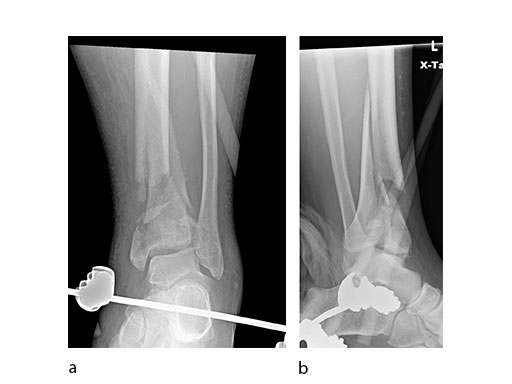

A 61-year-old laborer fell 5 meters from scaffolding. This was a closed injury with severe soft-tissue injury (Fig 67). He required three weeks of jointspanning external fixation prior to adequate resolution of edema.

Initial fixation was via a limited posteromedial exposure to buttress a posteromedial partial articular fragment (Fig 8). Following articular reduction and supplemental lateral column plate fixation via a limited anteromedial joint exposure, the VA-LCP Anteromedial Distal Tibia Plate was passed subcutaneous with subsequent percutaneous screw insertions into the plate shaft.